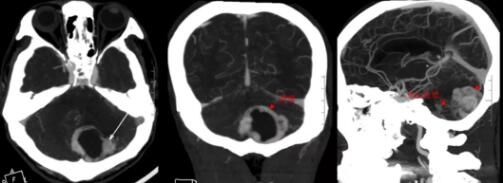

血管母细胞瘤是一类血供极为丰富的肿瘤,实质性血管母细胞瘤尤甚。术前完善的CTA检查,了解肿瘤血供相当必要。进一步的头颅CTA检查提示肿瘤的血供极为丰富,存在有多处供血动脉。然而,屋漏偏遭连夜雨,CTA检查还发现患者的前交通动脉上鼓了个小泡——也就是动脉瘤,也就是常常被脑外科大夫们形容为“不定时炸弹”的颅内病变,病死率相当高!

▲术前CTA:肿瘤血供丰富,多支供血动脉存在

▲术前CTA:前交通动脉瘤存在,大小3.2mm×3.4mm

于是,欧阳辉主任再次组织医护团队进行了讨论,患者颅内动脉瘤尚未破裂,并且动脉瘤大小约为3.5mm,手术破裂的风险相对较小。手术的首要目的在于切除后颅窝小脑肿瘤,解除占位效应及脑疝威胁,缓解脑积水。考虑到肿瘤血供极为丰富,存在多处供血动脉,应当配备充足血液,手术切除前应行肿瘤供血动脉的部分栓塞,以减少术中出血,提高手术成功率。